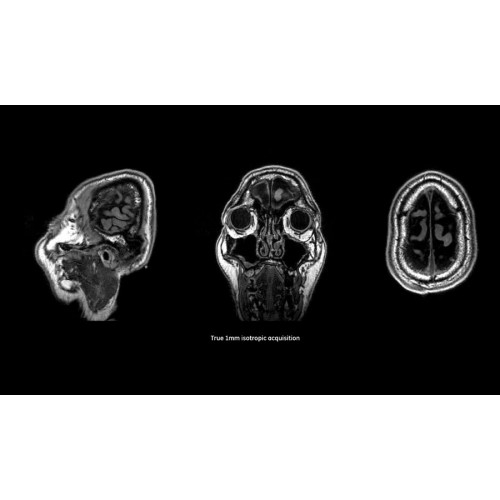

Детализация изображений

Система SIGNA Pioneer воплощает поразительные достижения в области визуализации. Передовая технология Total Digital Imaging (TDI) позволяет добиться большей четкости изображений и на четверть повысить соотношение сигнал/шум.

• Технология Digital Surround Technology (DST) — это новая технология объемной оцифровки данных, объединяющая сигналы от каждого элемента катушки. Прекрасное соотношение сигнал/шум и чувствительность поверхностных катушек в сочетании с превосходной однородностью и высокой проникающей способностью встроенной радиочастотной катушки — все это позволяет создавать качественные изображения не только позвоночника, но и всего тела.